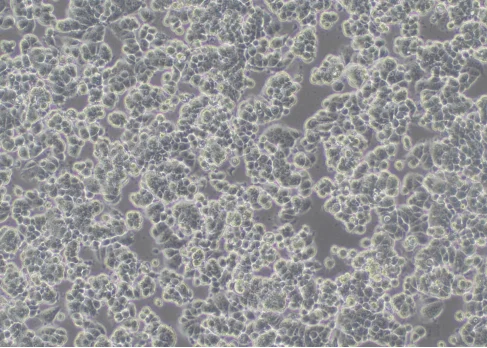

Figure 1: Cells grow normally (100×)

Appearing in the form of a loose three-dimensional cluster, growing in island shape in the early stage. As time goes by, gradually forming a flat monolayer, usually in regular shapes such as polygons or triangles.